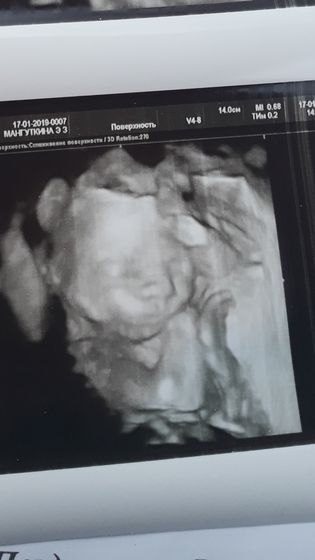

Ездили мы сегодня на 2ой скрининг, увидели нашего малыша, нам подтвердили мальчика?муж рад? будет у нас полный комплект? весим 360гр.24см, совсем кроха, прятал лицо руками, стесняшка наш?? ПДР 1.06.19г. Все у малыша хорошо? в заключении написали краевое прикрипление пуповины к плаценте, врач сказала что это не страшно, будем наблюдать в динамике почаще узи сказала после 3го скрининга!!! девочки, у кого так было??? это повлияло как то на малыша и как прошла беременность?

Фото класс